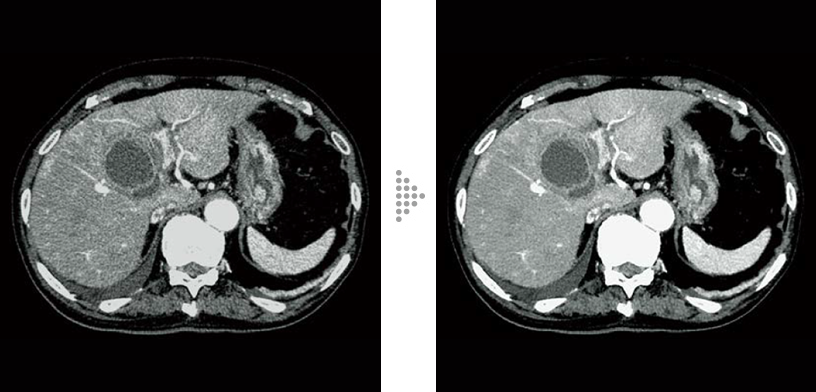

FBP(Left)

Intelli IPV(Right)

Renal cell carcinoma (80 kV)